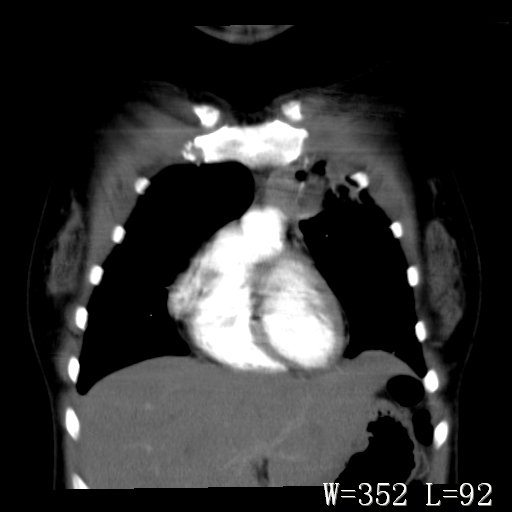

标题: CT27017:1、肺结核?2、永存左上腔静脉。 [打印本页]

标题: CT27017:1、肺结核?2、永存左上腔静脉。

女,32岁,自述肺结核治疗多年复查。

1)考虑左肺上叶肺脓肿,节段性肺不张。2)永存左上腔静脉。

1)考虑左肺上叶节段性肺不张。原因?2)永存左上腔静脉。

支持肺脓肿;还是双上腔静脉确切些吧,回流至冠状窦或右心房。

考虑左肺上叶胸腺瘤可能性大。肺不张/永存左上腔静脉

胸骨后偏左侧囊实性病灶,考虑胸腺瘤可能性大.

1、胸骨后偏左侧囊实性病灶,考虑胸腺瘤可能性大。2、永存左上腔静脉。